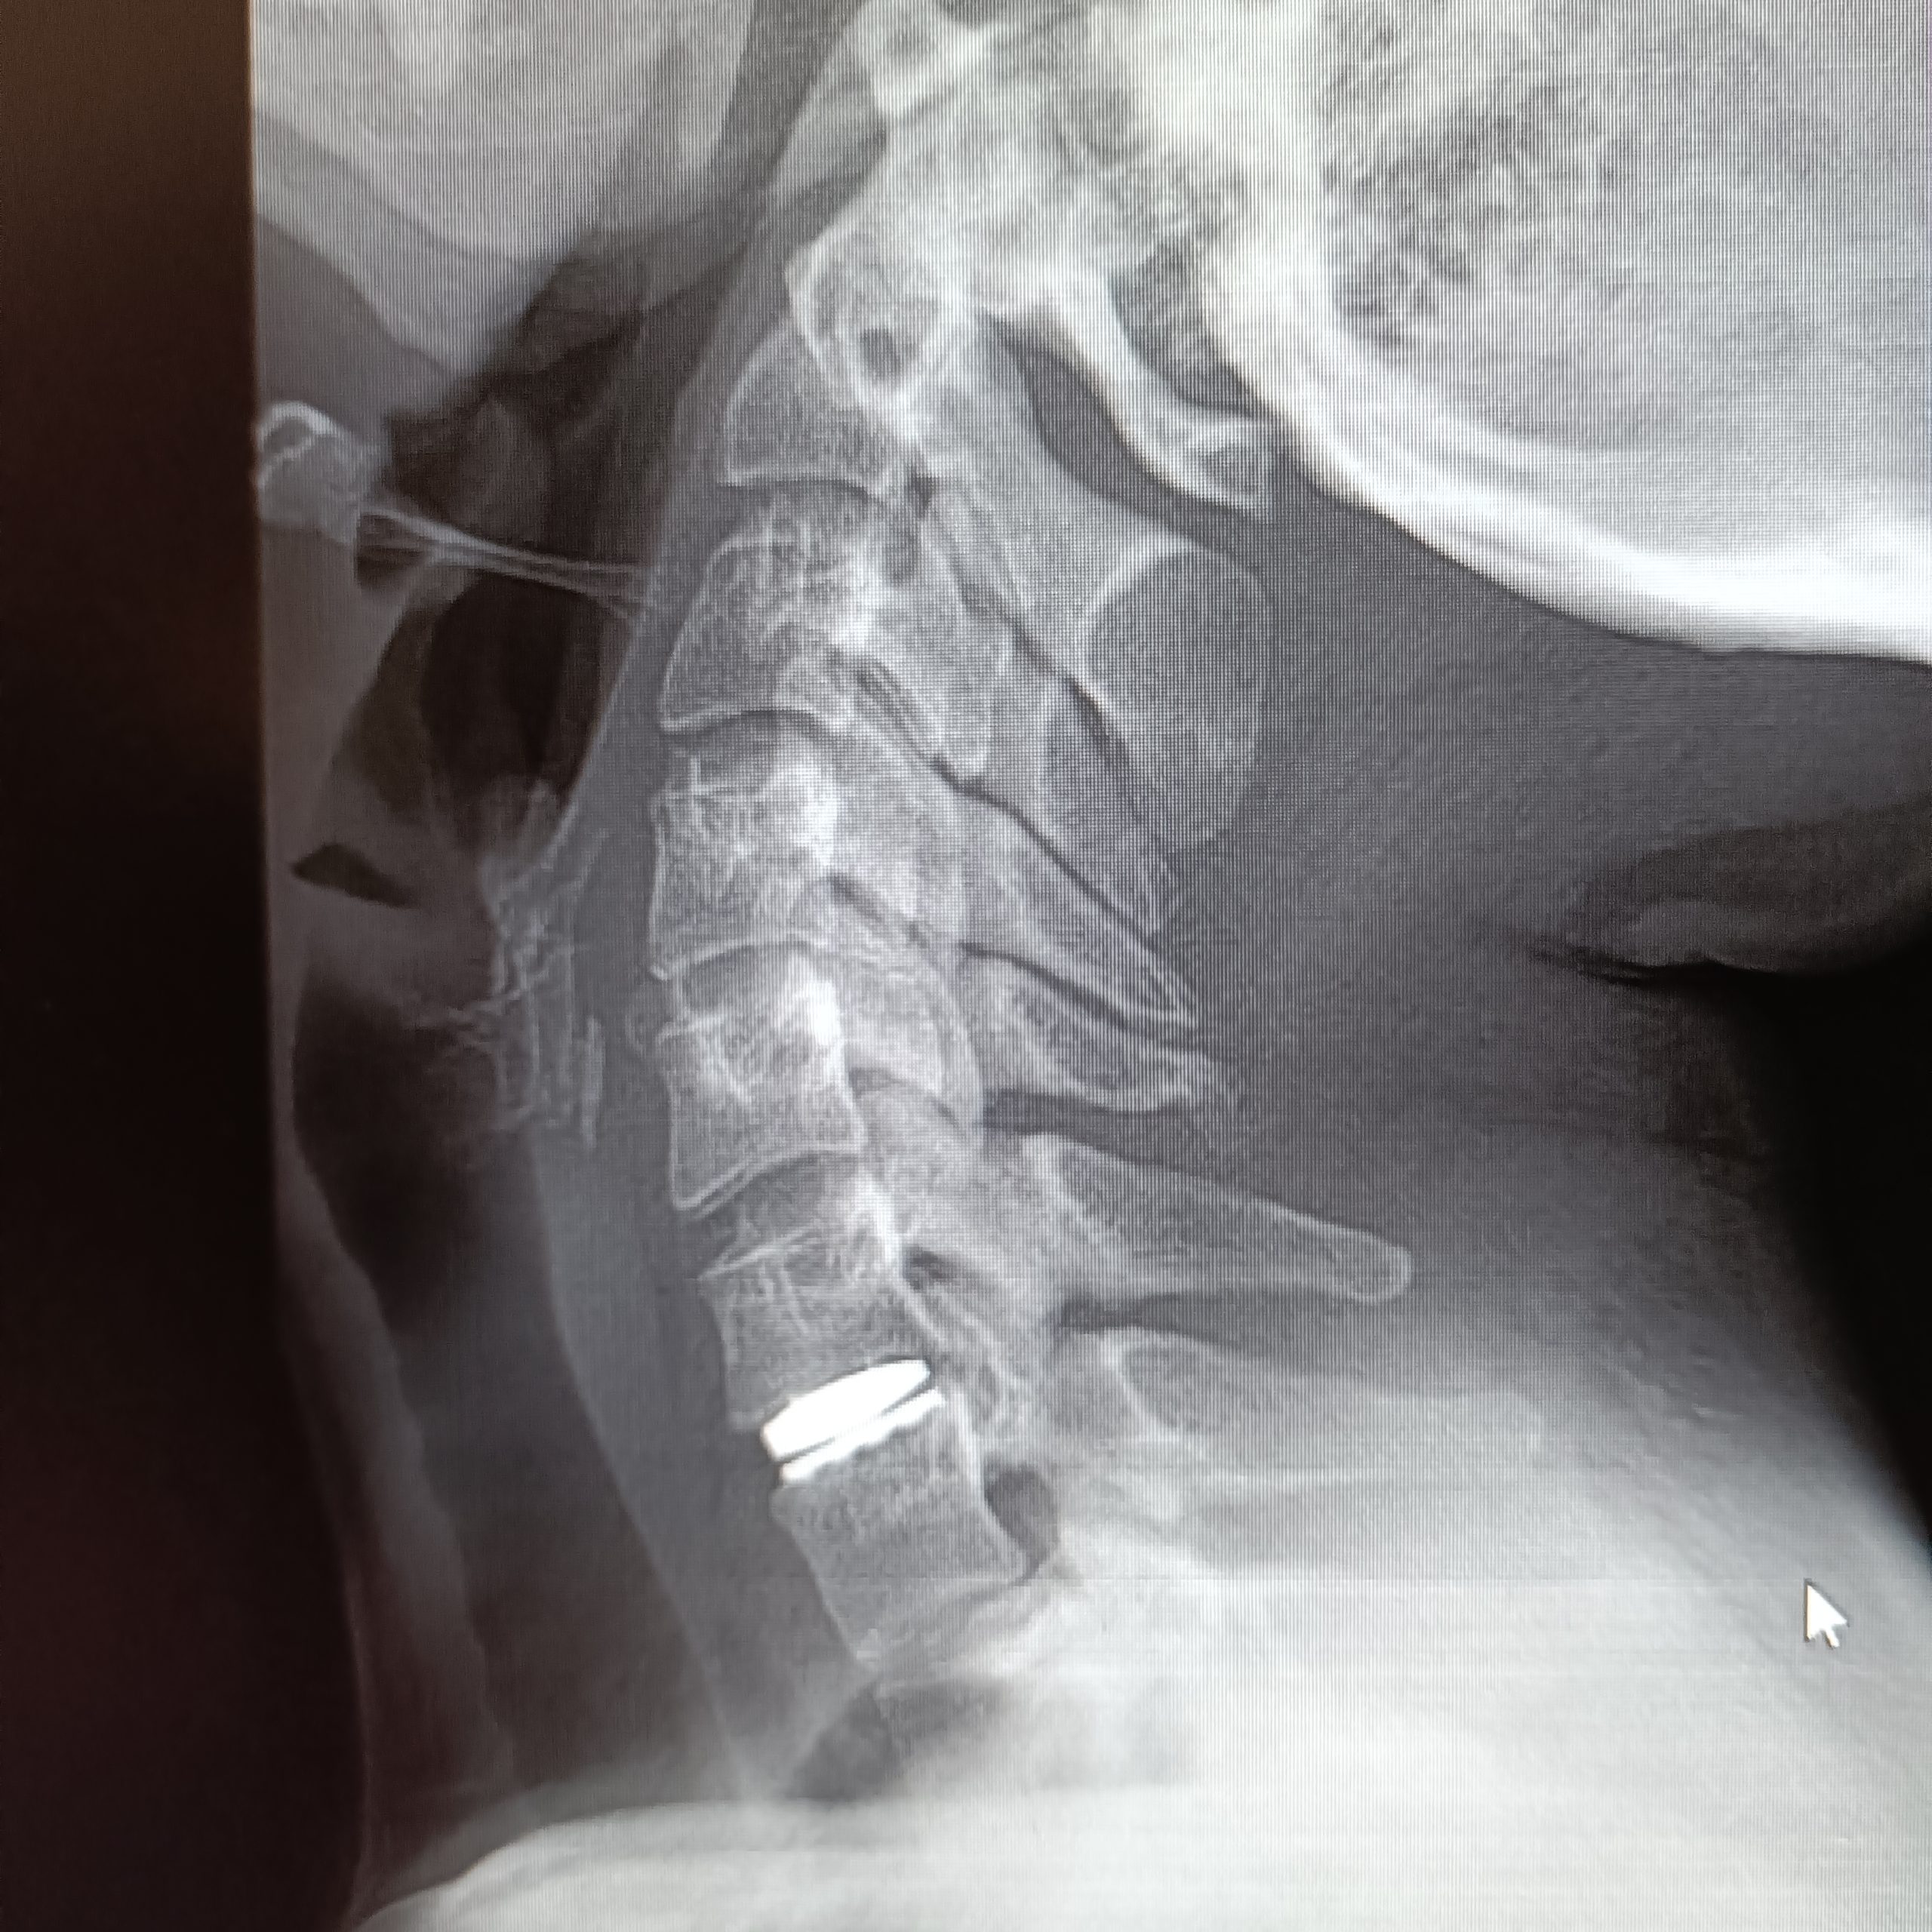

Boyun fıtığının cerrahi tedavisinde amaç, sinir kökünün üzerinde oluşan mekanik basıyı kaldırmak ve sinir kökünü rahatlatmak. Söz konusu bu bası erken dönemde kaldırıldığında sinir dokusu içerisinde daha ileri dönemlerde ortaya çıkabilecek olası kronik ve hatta kalıcı olabilecek değişikliklerin de önüne geçilmiş oluyor. Tedavi geciktiğinde ise -hasta en sonunda ameliyat olsa dahi- bu gecikmeden kaynaklı sinirde oluşan hasar nedeniyle, hastanın ameliyattan faydalanamaması söz konusu. Bu nedenle mutlaka her hasta için en doğru tedavinin ne olacağına, ne zaman ve nasıl yapılacağına karar vermek hayati önem taşıyor. Cerrahi tedavide, boynun ön veya arka tarafından yapılabilen yaklaşımlar var. Arka taraftan yapılan ameliyatlar sinir dokusunun çıktığı kanalın mikrocerrahi tekniklerle genişletilerek sinir üzerinde boyun fıtığından oluşan baskının indirekt yolla giderilmesine dayanıyor. Boynun ön tarafından uygulanan klasik cerrahide ise, iki omurga arasındaki disk tamamen çıkarılıyor ve fıtıklaşmış kısma ulaşılarak sinir rahatlatılıyor. Taşan bölüm temizlendikten sonra iki omurga arasında oluşan boşluğu doldurmak için hastanın kendi vücudunun başka bir yerinden alınan bir kemik parçası (genellikle kalçadan) veya plastik/metal kafesler kullanılıyor. Sonrasında buradaki iki omurganın birbirine tam olarak kaynaması (füzyon) için 2-3 ay beklenmesi gerekiyor. Bu tip bir ameliyat sonrasında boynun hareket kabiliyeti ameliyat edilen her bir seviye için 10-20 derece arasında azalıyor. Bu kayıp, günlük hayatta genelde bir sıkıntı yaratmasa da zaman içinde, ameliyat edilen mesafenin bir üst ile bir alt seviyesinde artan yüklenme ve esnemeye bağlı olarak boyun fıtığı oluşma riskini artırıyor. Bunun tıbbi adı “komşu segment hastalığı.” Bu risk tek seviyede yapılan klasik füzyon ameliyatlarından sonraki her yaşam yılı için %2,9. Birden çok seviyde yapılan füzyon bu yıllık riski daha da artırıyor. Yani her ne kadar başarılı olursa olsun yapılacak servikal füzyon ameliyatı sonrasında er ya da geç ikinci bir ameliyat olma olasılığı yüksek.

Günümüzde boyun fıtığı cerrahisinde hem erken dönemde hareket kabiliyetinin kısıtlanmadan en doğal şekliyle korunması hem de söz ettiğimiz “komşu segment hastalığı”nın önlenmesi açısından tercih edilen yöntem servikal disk protezleri. Bu protezler vücudun kabul ettiği, herhangi bir alerjik reaksiyon yaratmayan özel plastik ve seramik alaşımlar ile titanyum gibi hafif ve çok dayanıklı malzemelerden üretiliyor.